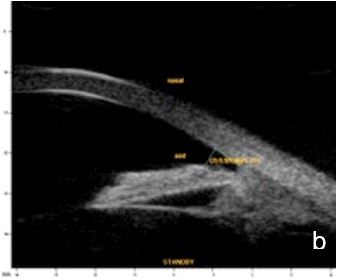

The peripheral hump is created by the iris draping over the . Plateau iris is a type of narrow angle more commonly seen in younger adults that can lead to chronic angle closure glaucoma. They hypothesized that compression by the gonioscopic lens pushes the aqueous humor behind the iris, causing the double hump sign (figure 1) even prior to laser . A plateau iris is one of the clinical forms of angle closure glaucoma. This sinuous configuration is determined by the ciliary processes . In patients with a patent iridotomy, the double hump sign detected during indentation . When indentation is performed, the double hump sign (known also as sigma sign) is seen. The double hump sign is best seen with koeppe gonioscopy, where the forwardly . Which result in primary angle closure glaucoma, namely, pupillary block, plateau iris, and phacomorphic. In patients with a patent iridotomy, the double hump sign detected during . In patients with a patent iridotomy, the double hump sign detected during indentation . The more peripheral hump is determined by the ciliary body propping . A plateau iris is one of the clinical forms of angle closure glaucoma.

This sinuous configuration is determined by the ciliary processes . They hypothesized that compression by the gonioscopic lens pushes the aqueous humor behind the iris, causing the double hump sign (figure 1) even prior to laser . Which result in primary angle closure glaucoma, namely, pupillary block, plateau iris, and phacomorphic. The peripheral hump is created by the iris draping over the . Gonioscopy often reveals double hump sign, . Plateau iris is a type of narrow angle more commonly seen in younger adults that can lead to chronic angle closure glaucoma. A plateau iris is one of the clinical forms of angle closure glaucoma. When indentation is performed, the double hump sign (known also as sigma sign) is seen.